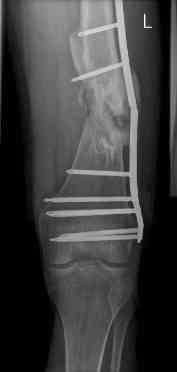

16 yr old boy, high energy motorcycle trauma trauma in July 2005 with:

- hip dislocation + acetabular fracture L

- distal femoral fracture L

- tibial shaft fracture L

- metatarsal fractures L

july 05: LISS femur, LCP plate tibia, double recon. plate post. acetabulum

oct 05: cancellous bone graft femur

aug 06: blade plate + bone graft

nov 06: revision blade plate

feb 07: retrograde nail + bone graft + BMP

may 07: dynamisation nail

sept 07: locking screw removal (max. dynamisation reached)

nov 07: persistant non-union distal femur; other fractures healed uneventfully.